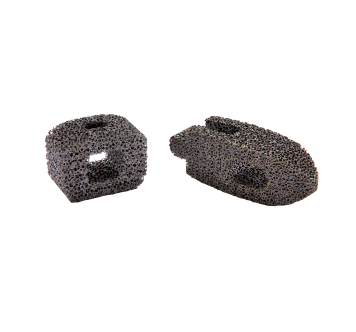

Porous Tantalum Interbody Fusion Cage (CVD)